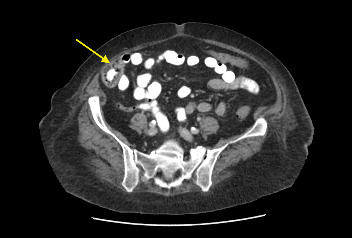

Patient had a complicated in-hospital stay which was further complicated by septic shock secondary to hospital acquired pneumonia and pericardial effusion. A repeat ultrasound liver three weeks later demonstrated a decrease in the size of the liver lesions, suggested that they favour abscess rather than metastasis. Repeat CT abdomen again confirmed the findings and also noted lobulated mucosal thickening at ileocaecal junction, suggestive of colonic neoplasm. Caecal mass was also identified in the initial CT retrospectively, which was missed initially. Colonoscopy confirmed a non-obstructing, non-circumferential mass in the caecum. Histology showed adenocarcinoma. Her liver abscess completely resolved with long course intravenous antibiotics. CT staging did not show any evidence of distant metastasis (See figure 2). An elective uncomplicated laparoscopic right hemicolectomy was performed, and she was subsequently discharged home well day six post op. Histology returned to show pT2N0M0 adenocarcinoma.

Figure 2: (a, b) Red arrow - Interval CT 2 months later illustrated significant reduction in liver mass in keeping with resolving abscesses. (b, c) Yellow arrow - Large polypoid lesion within the caecum at the ileocaecal region in keeping with carcinoma